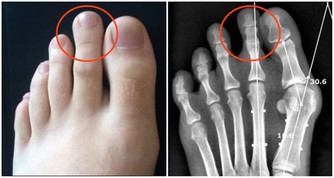

小指以指節長短相稱、直而不偏曲為佳。

小指過度彎曲:女性卵巢功能差,易患不孕症;男性性功能障礙,易患陽痿早洩等。